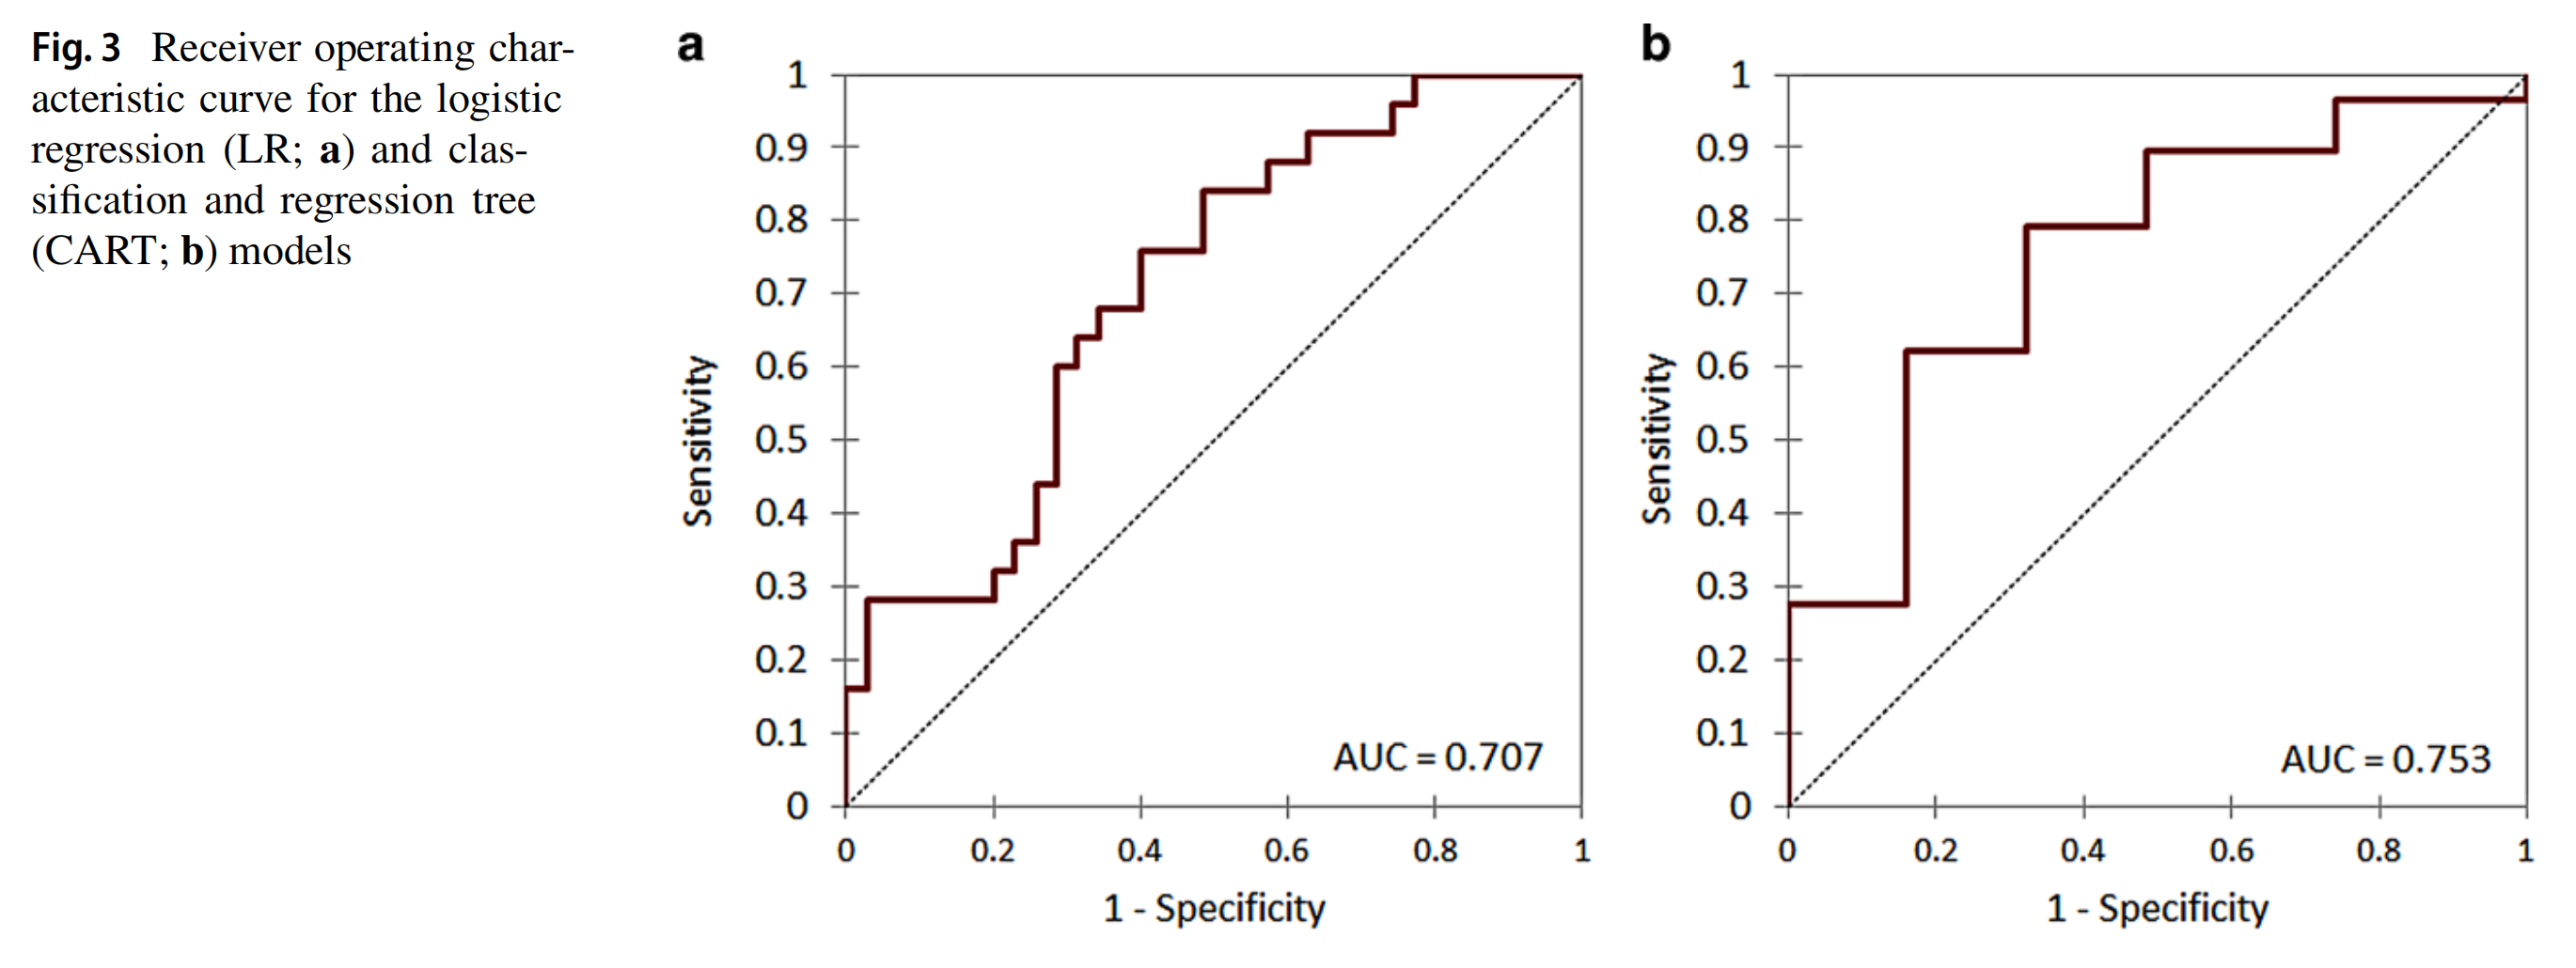

LR和CART模型的分类性能在表3中报告了训练和内部验证数据集。CART分类器表现最佳,准确度、精确度、召回率和F1分数分别为79.2%、78.4%、80.3%和78.5%。

两个模型的接收器操作特性(ROC)曲线交叉验证结果在图3中展示。LR和CART模型的曲线下面积(AUC)分别为0.707(95% CI: 0.633–0.817)和0.753(95% CI: 0.675–0.836)。

使用这四个顶级特征,我们训练和评估了两个机器学习模型,使用LR和CART分析方法。最佳的诊断性能是由CART分类器实现的,其在训练集和评估集中的准确度、精确度和召回率分别为0.792、0.784和0.803。获得的CART模型具有明显的优势,即易于解释,与机器学习或深度学习的其他方法不同。我们使用四个放射组学协变量,通过九个节点和三个深度级别构建了CART模型,以产生一个直接和紧凑的决策树。CART分析选择SVR大于0.383的病变与完全缓解相关。随后,偏度和相关性在提高病变分类率方面发挥了重要作用,高偏度和低相关值有利于完全缓解。